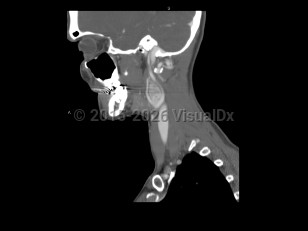

Imaging Studies image of Carotid body tumor - imageId=7872301. Click to open in gallery.  caption: '<span>Sagittal post-contrast CT image  demonstrates an enhancing mass in the carotid space, splaying the  internal and external carotid arteries. Findings are consistent with a  carotid body tumor.</span>'

Sagittal post-contrast CT image demonstrates an enhancing mass in the carotid space, splaying the internal and external carotid arteries. Findings are consistent with a carotid body tumor.